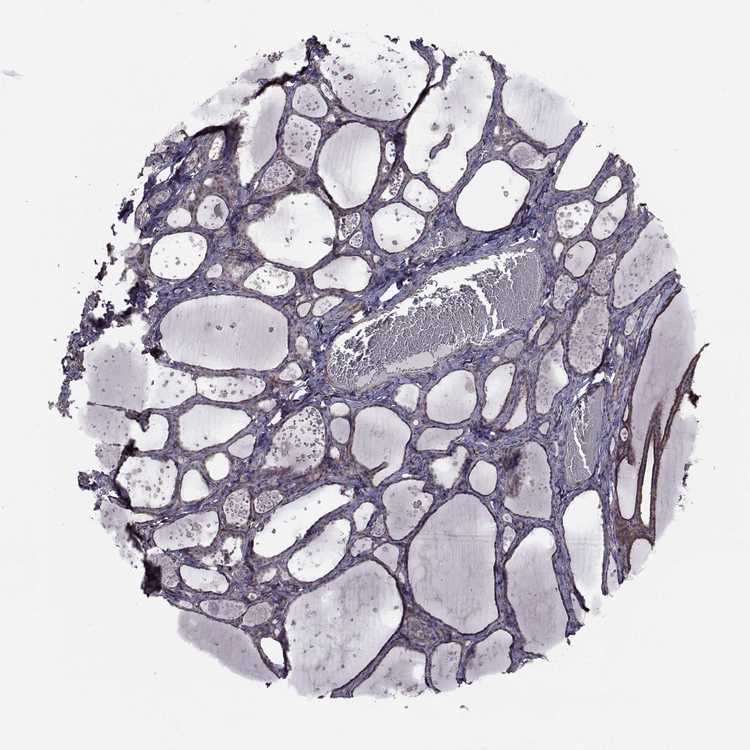

THYROID GLAND - Antibody stainingi

Antibody staining in the annotated cell types in the current human tissue is reported as not detected, low, medium, or high, based on conventional immunohistochemistry profiling in selected tissues. This score is based on the combination of the staining intensity and fraction of stained cells.

Each image is clickable and will lead to virtual microscopy that enables deeper exploration of all samples and also displays staining intensity scores, fraction scores and subcellular localization as well as patient and tissue information for each sample.

Antibody HPA072625Antibody HPA073886

Glandular cells LowNot detected